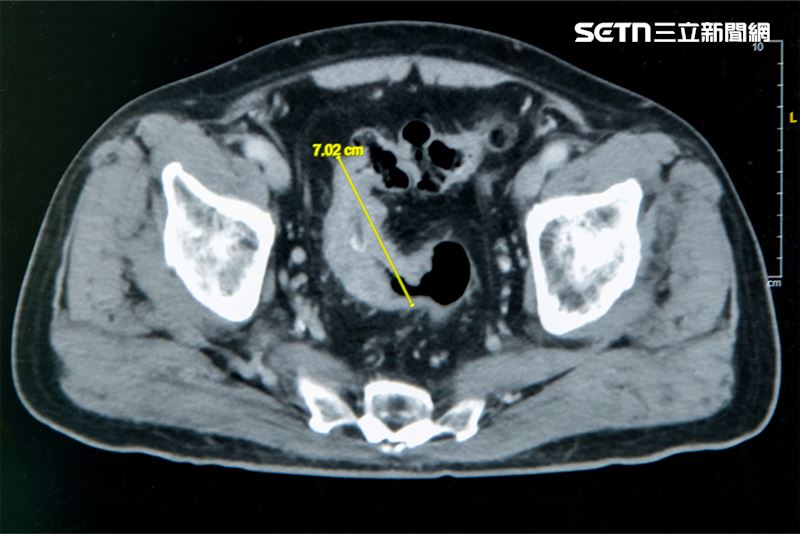

大腸直腸外科主任張譽耀醫師表示,老翁罹患乙狀結腸癌,腫瘤約7公分,造成腸子幾乎完全阻塞,老翁一進食肚子就會脹痛,因為不敢進食,體重下降、營養不足,很可能造成傷口癒合不良。